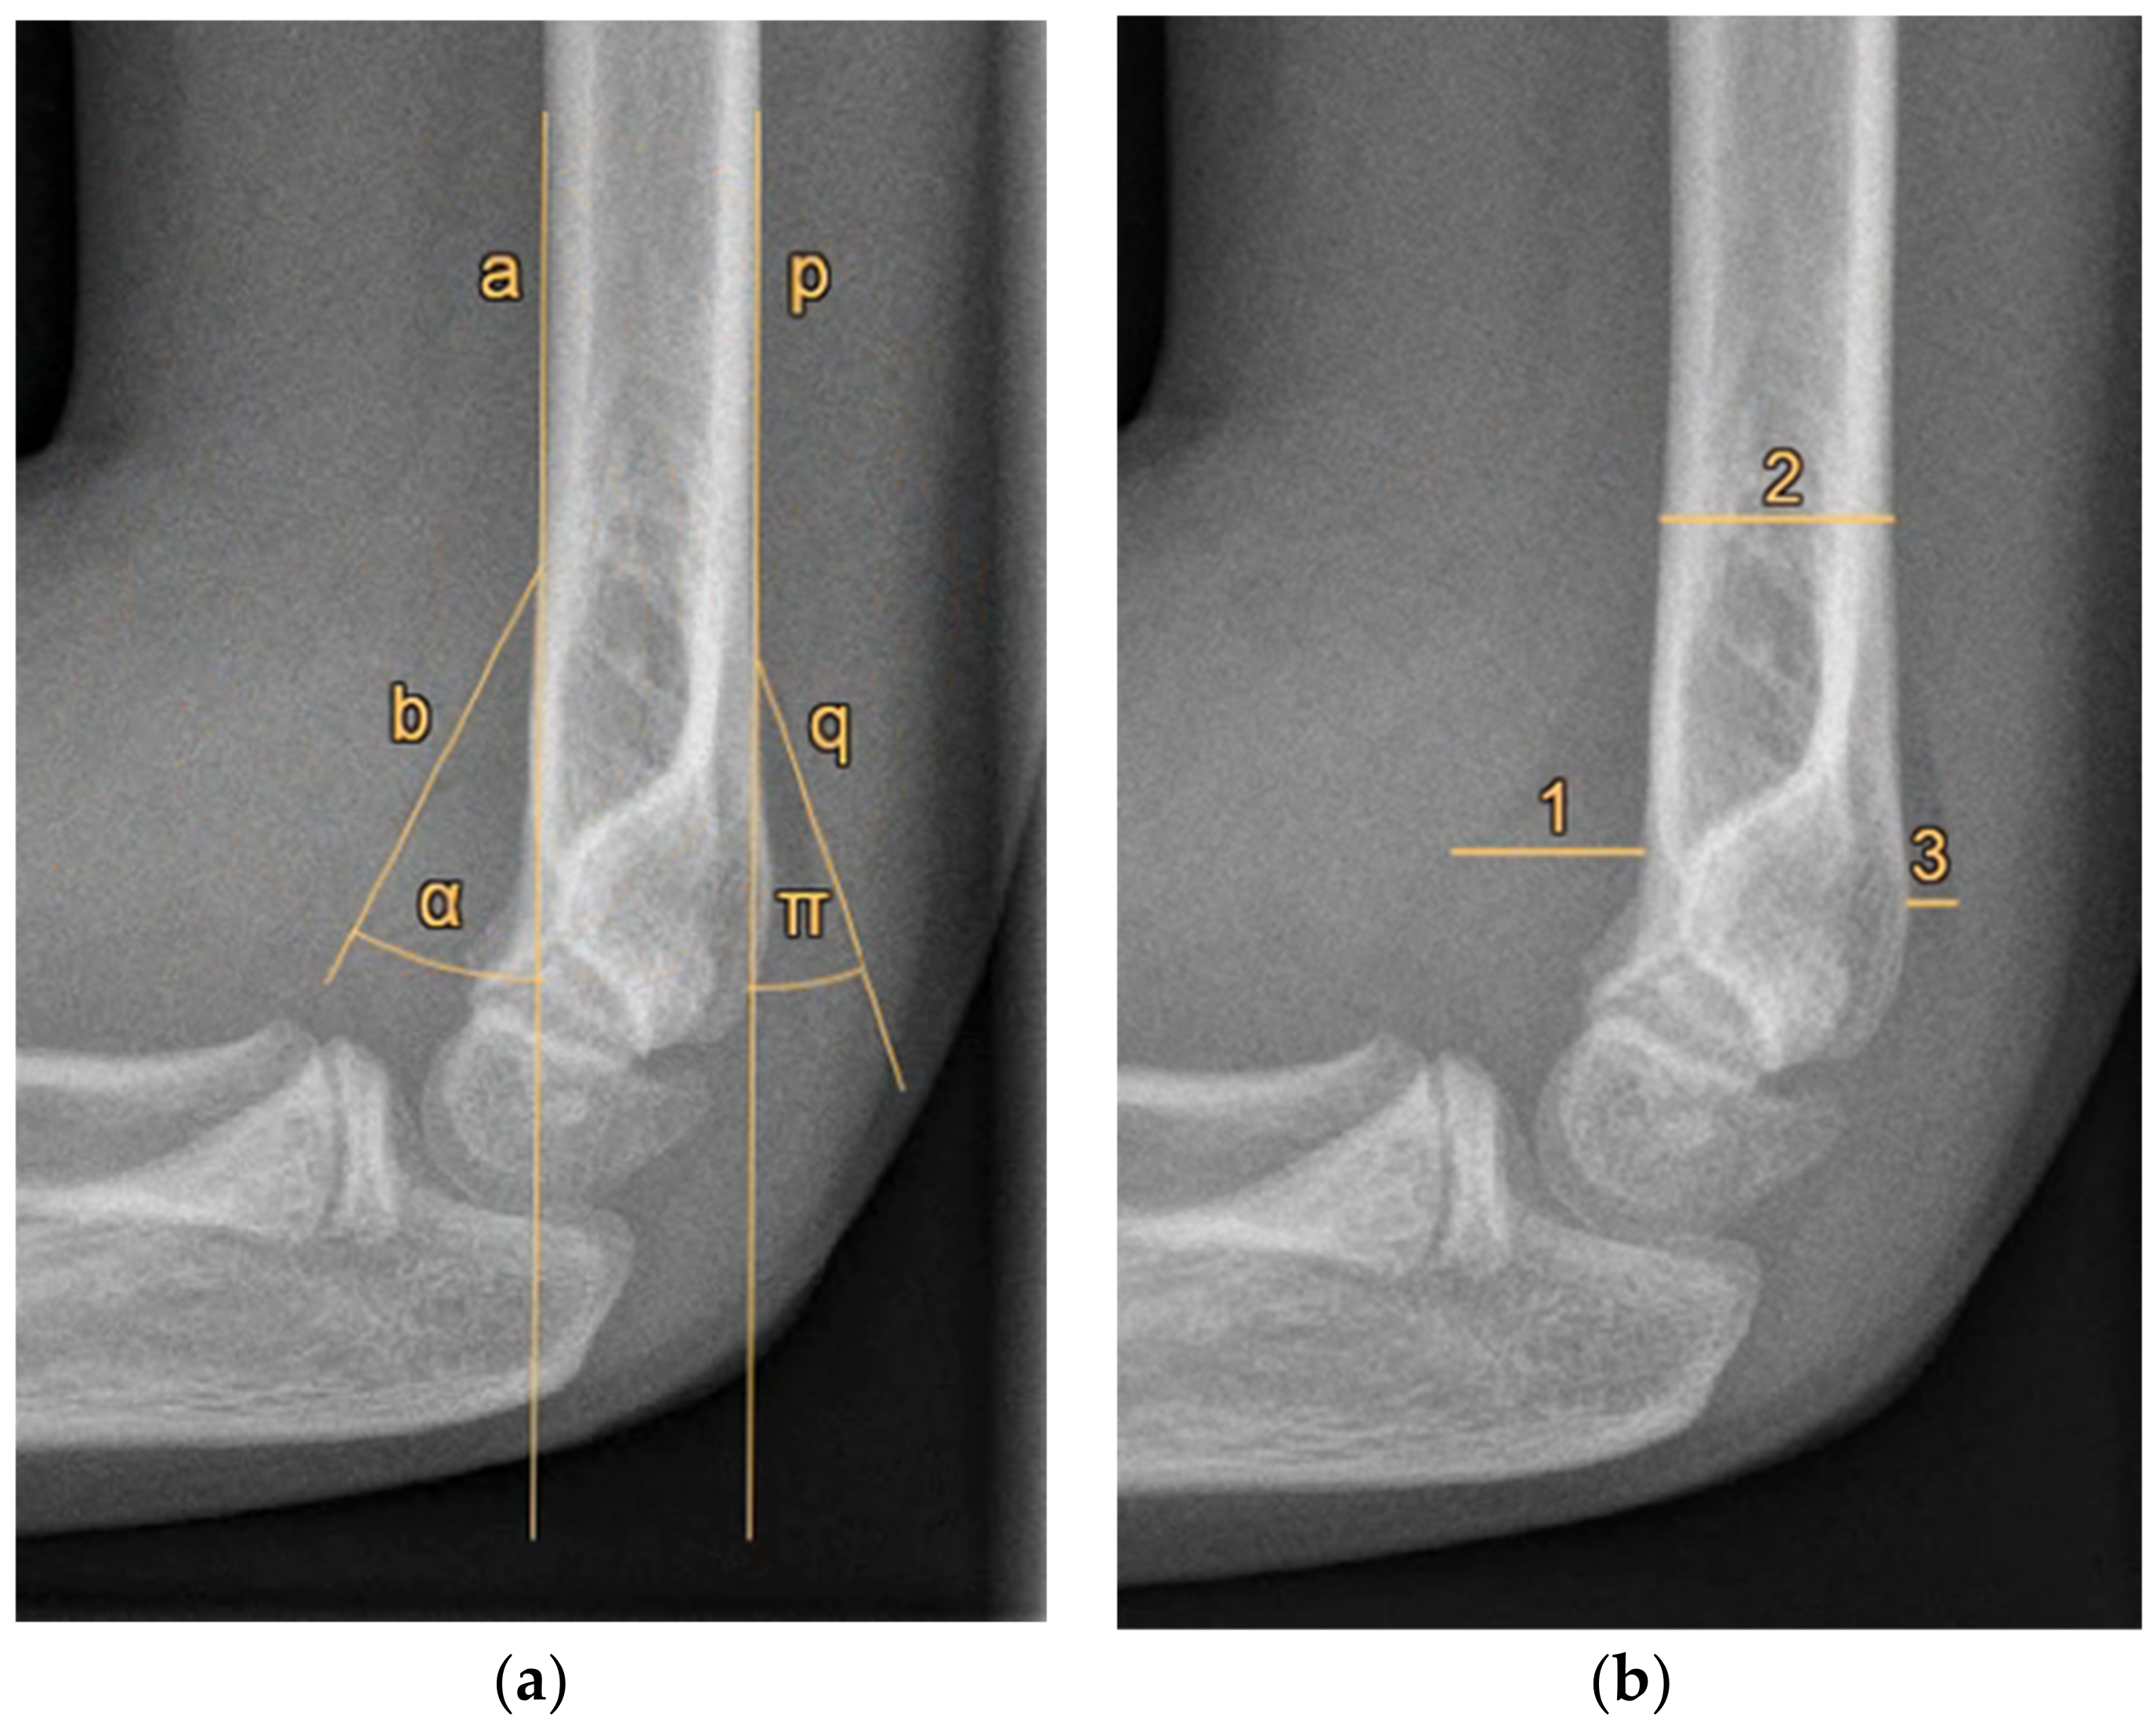

Furthermore, radiographic measurements were performed on the same radiographs by the research team to identify cut-off values for a positive FPS. Three paediatric orthopaedic trauma and elbow surgeons and two trained researchers (blinded to the respondents’ answers) independently measured two possible objective measures of an FPS on each of the 20 radiographs, namely, (1) the angle between the fat pad and humerus, and (2) the size of the fat pad relative to the humerus diameter (Figure 1). The averages of the five researchers’ measurements were used as the final measurement of each radiograph. The radiographs were measured again eight weeks later by the first author in a different order; the author was blinded to the first series of measurements to assess test–retest reliability.

Figure 1. Radiographic measurements of the anterior and posterior fat pad signs. (a) Angle measurements. a: line along the anterior side of the humerus shaft; b: line indicating the anterior fat pad; α: angle measurement of the anterior fat pad; p: line along the posterior side of the humerus shaft; q: line indicating the posterior fat pad; π: angle measurement of the posterior fat pad. (b) Distance measurements—1: maximum perpendicular distance of the anterior fat pad to the humerus; 2: humerus diameter measured at the proximal level of the anterior fat pad; 3: maximum perpendicular distance of the posterior fat pad to the humerus. The anterior fat pad distance was indicated by 1 divided by 2; the posterior fat pad distance was indicated by 3 divided by 2.